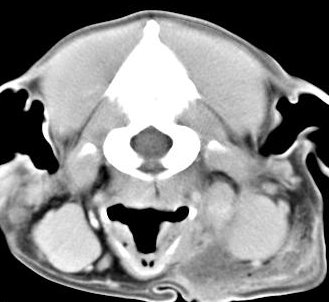

imágenes de TC en el perro | ||||||||||

ejemplo de imágenes de TC en el perro. Nótese la celulitis en la región parotídea izquierda | ||||||||||